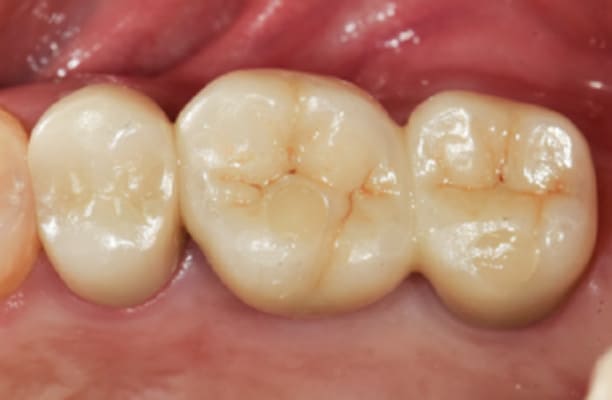

13+ 年

-

种植体植入 2012年10月 -

最终修复体 2013年1月 -

随访:13年 2025年3月